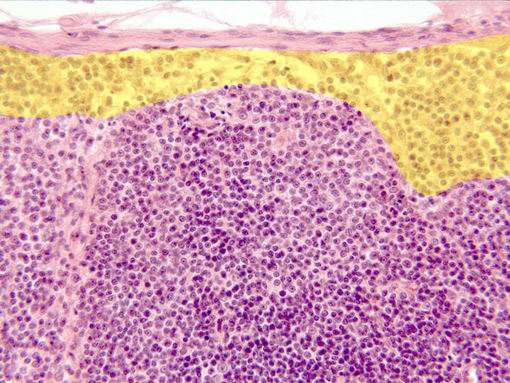

Aspect of the zone next to the ganglionary

capsule

observed with the objective of 40x. Under the capsule appear

the

subcapsular sine

(yellow),

a looser arranged zone, and immediately underneath is

situated part of a

lymphatic follicle,

containing numerous lymphocytes showing blue-stained nuclei